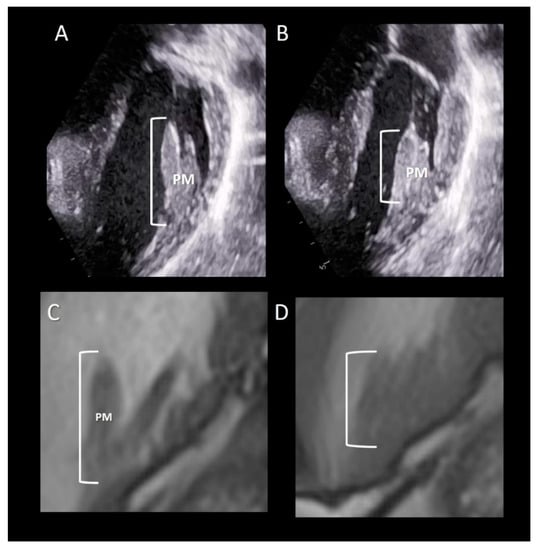

Imaging Techniques

All the three imaging modalities may beautifully illustrate PMs. Two-dimensional TTE/TEE and CMR, because of their high frame rate, may assess the shortening of the PM (Figure 8). Conversely, the high spatial resolution of CT allows for the obtaining of exceptional images of the variable anatomy of the PMs attachment on ventricular myocardium (Figure 9).

Figure 8.

(A,B) 2D TTE and (C,D) CMR cross-sections in diastole (A,C) and in systole (B,D) showing the longitudinal contraction of papillary muscle (PM) preventing leaflet eversion during the systole (see text).